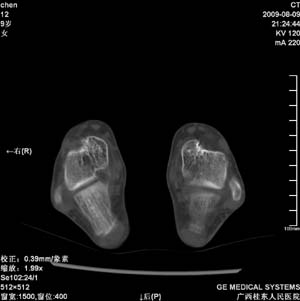

标题: PED2867:右侧内踝肿胀,骨质改变,请各位老师会诊 [打印本页]

标题: PED2867:右侧内踝肿胀,骨质改变,请各位老师会诊

九岁小朋友,近期左侧内踝疼痛,局部肿胀,平时无特殊,近期经常溜干冰

对不起,是右侧内踝肿胀

未见明显异常。

双踝关节骨质及发育未见异常。